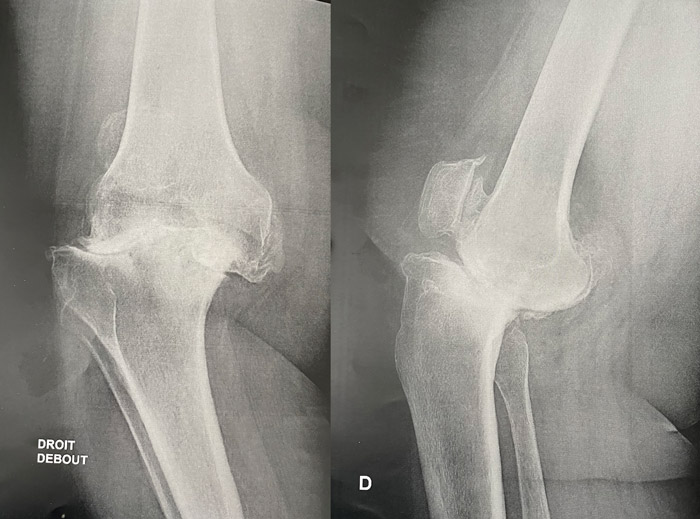

Right knee X-rays

• ✔️Kellgren and Lawrence grade 4

• ✔️Ahlback grade 4

Seeing the posterior cup, what other exams would you do?

• ✔️3D planning thanks to a CT scan

• ✔️X-ray telemetry of the lower limbs